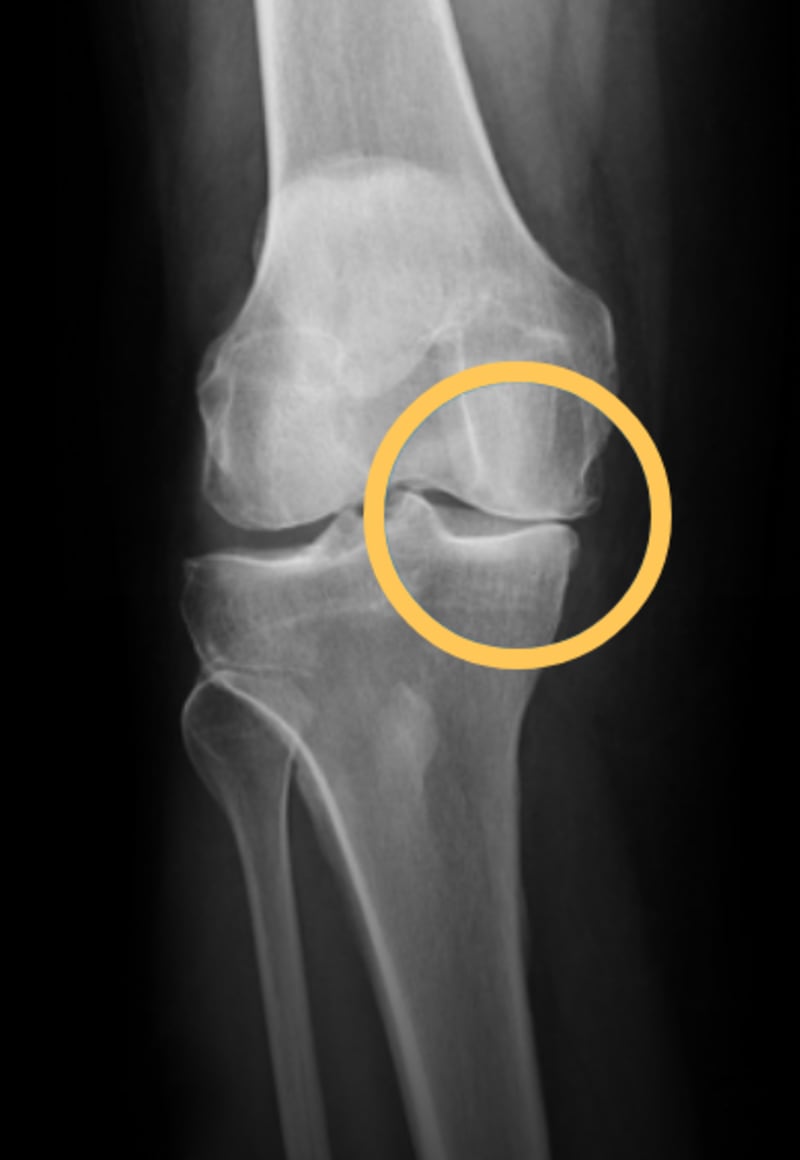

Knee OA with bracing

(space created between bones)